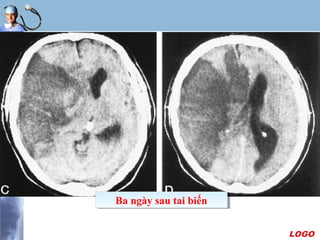

Xác định thời gian nhồi máu

 Phân biệt nhồi máu mới và cũ

- Giảm đậm độ ít : vài giờ

- Giảm đậm độ dễ nhận thấy : vài ngày

- Giảm đậm độ nhiều : một tới hai tuần

- Nhuyễn não : trên một tháng

 Fogging effect: hiện tượng đồng đậm độ vùng nhồi máu

ở ngày 14-21 do tăng thực bào hoặc xuất huyết vi thể,

khi đó vùng nhồi máu rất khó nhận thấy.

 Một số trường hợp có hiện tượng tăng quang do xuất

huyết trong vùng nhồi máu vào sau ngày thứ ba.

Ba ngày sau tai biếnBa ngày sau tai biến

LOGO